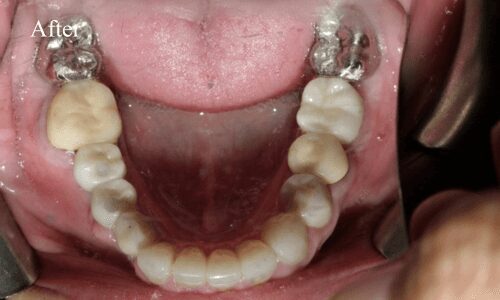

Full Mouth Rehabilitation

Full mouth rehabilitation or FMR is a restorative dental procedure which involves replacing all the teeth in the upper and lower jaws.This is a comprehensive treatment that combines general, cosmetic and restorative dentistry. This means you may have to get dental crowns, implants and whitening done at the same time to bring back the original strength, functionality, and aesthetic appeal of your teeth.